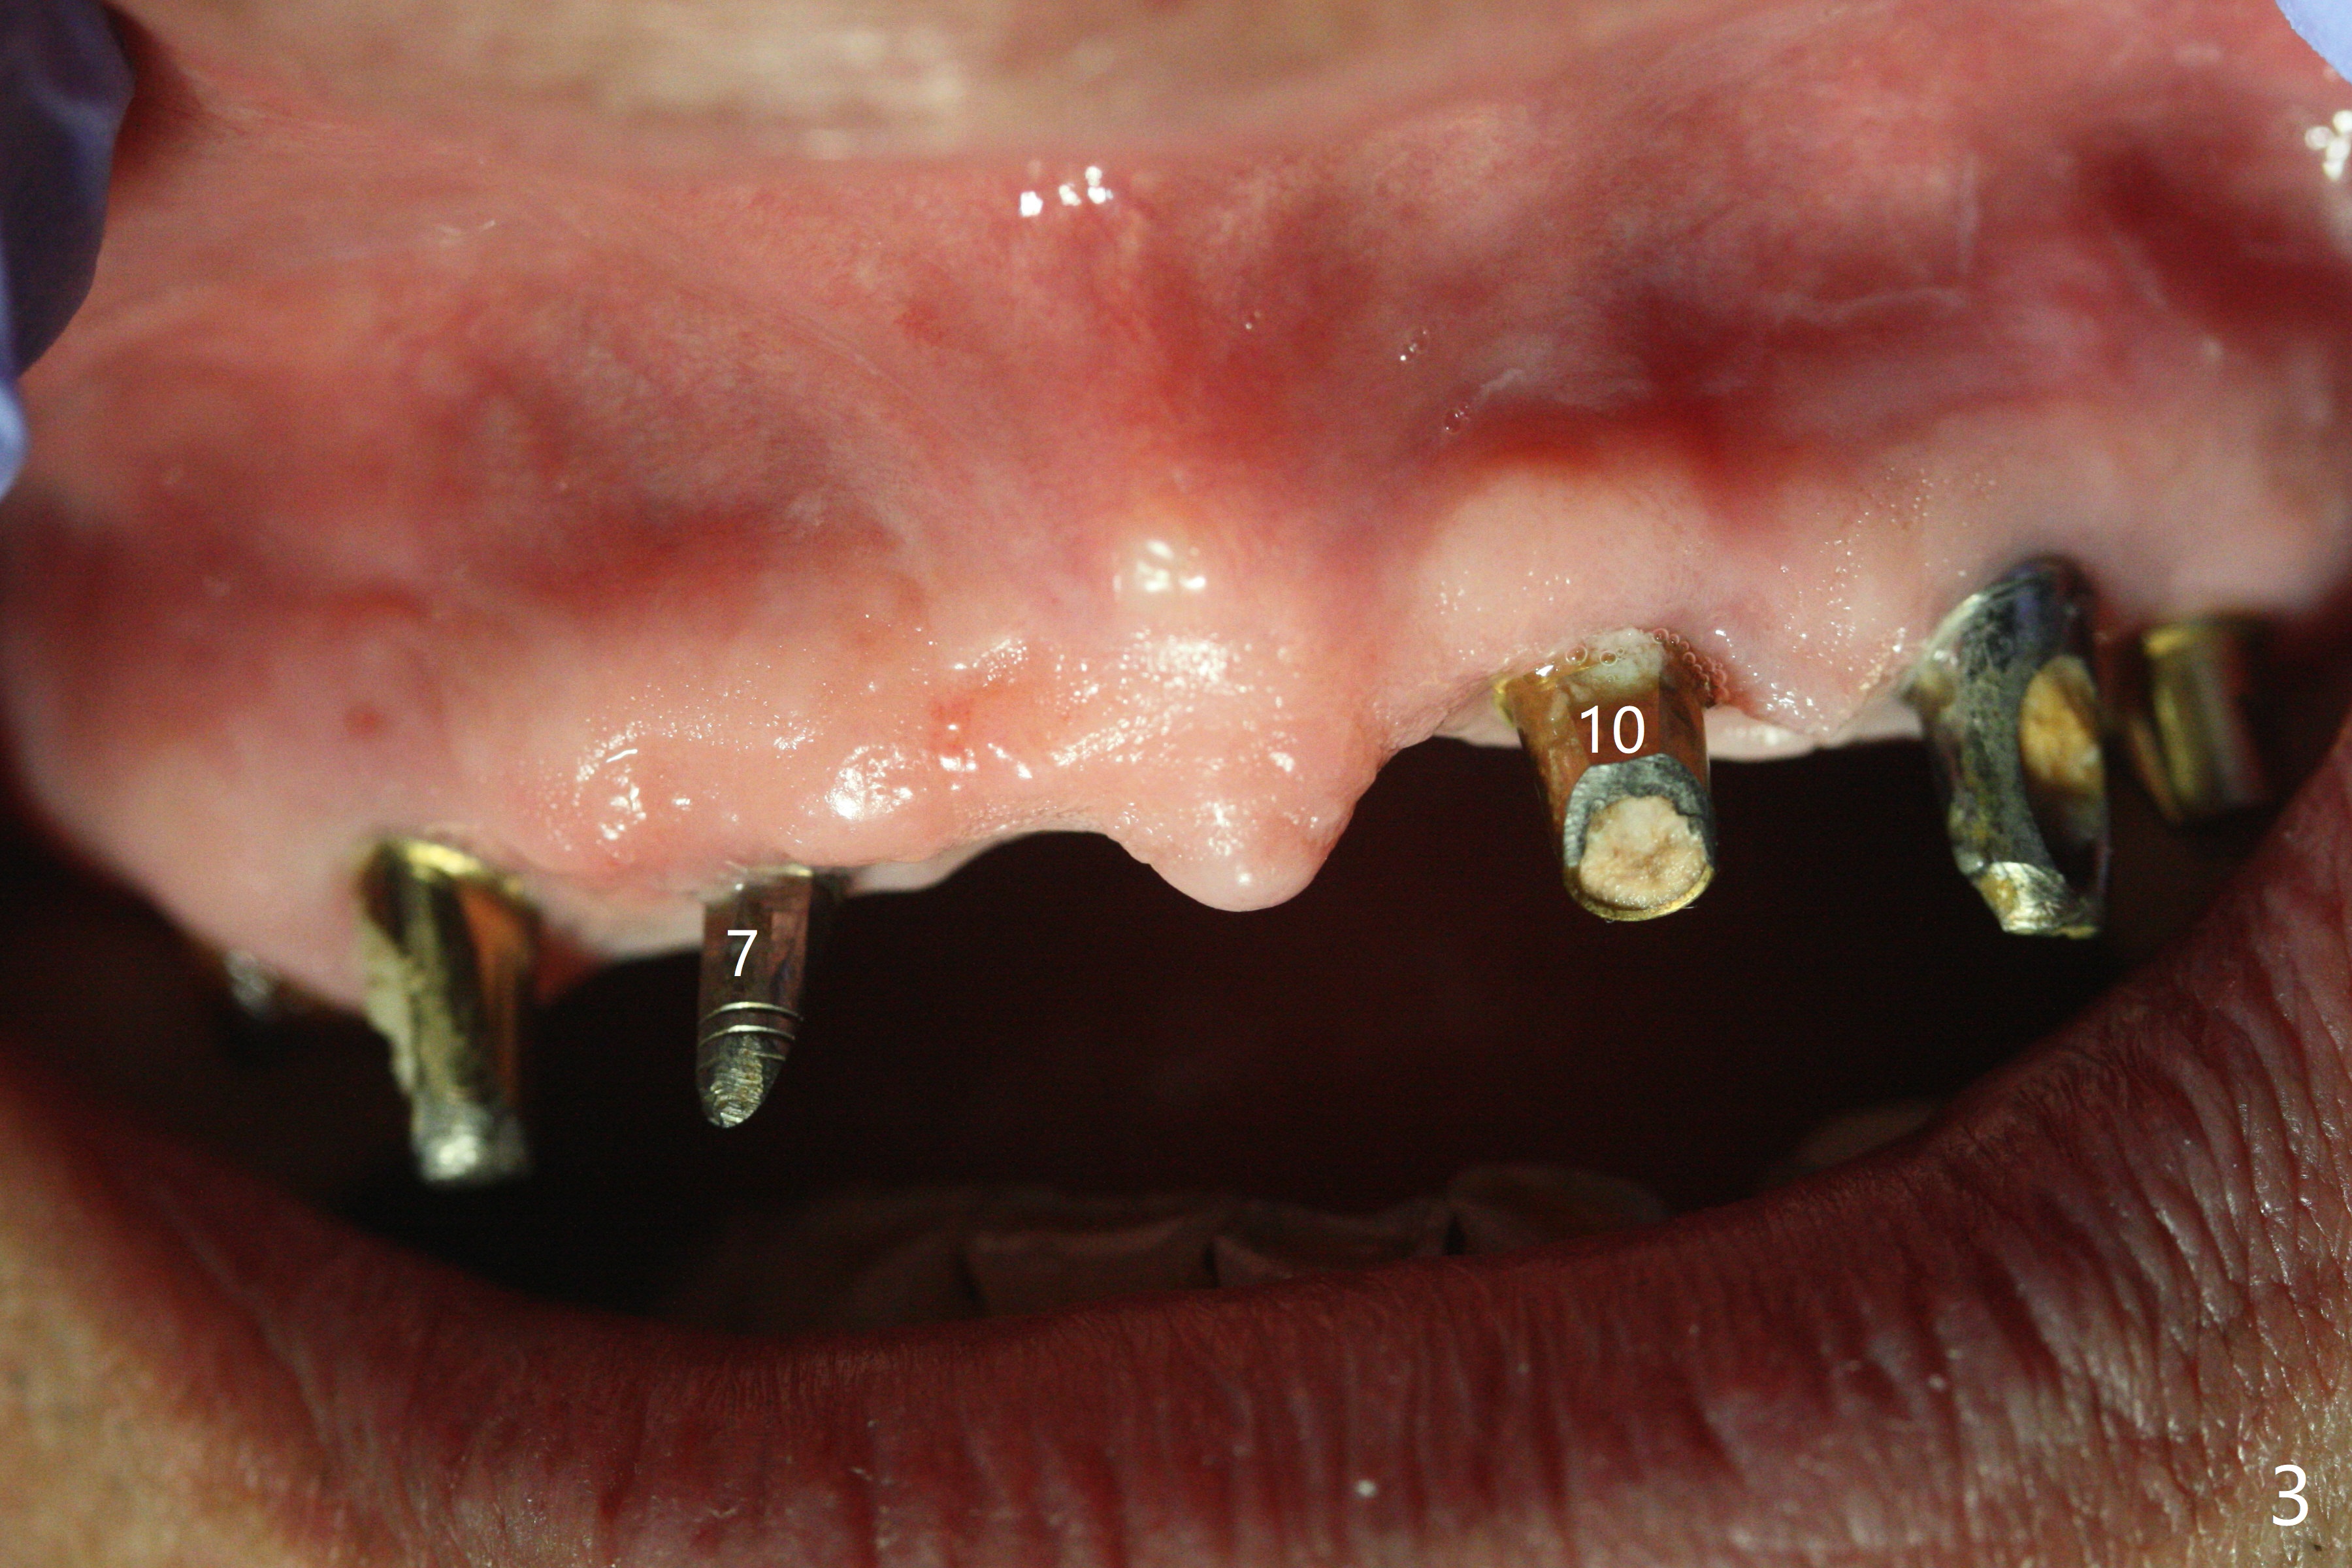

With temporarization of #3,4,13-15 (Fig.1), the anterior clearance is maintained (Fig.2). When provisional is removed, there is no papilla between #7 and 8 (Fig.3,4). After confirmation of complete seating of the abutments at #6 and 10 (Fig.5,6), gingivectomy is conducted with Diode laser (Fig.7,8). Following provisional being relined and modified, the anterior papillae form (Fig.9).